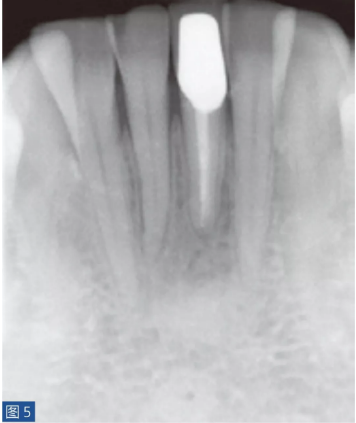

圖5:31 牙齒AAP。根管再治療12 個(gè)月后。